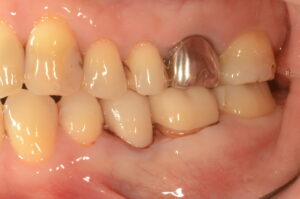

Before

| 主訴 | 歯並びを治したい |

|---|---|

| 診断名 | 叢生(混雑した歯並び) |

| 年齢・性別 | 82歳、女性 |

| 治療期間・回数 | 4ヶ月間、来院回数4回 |

| 治療方法 | 歯と歯の間に0.5mmのやすりがけをして歯の横幅を修正し、マルチブラケット装置(ワイヤー矯正器具)にて歯を配列 |

| 費用 | 検査料 55,000円 基本矯正料 220,000円 処置料 5,500円 / 月 |

| デメリット・注意点 | 唇に装置が当たって口内炎になる可能性 歯根吸収の可能性 調整のたびに2〜3日程度、上下の歯が接すると痛みが生じる |